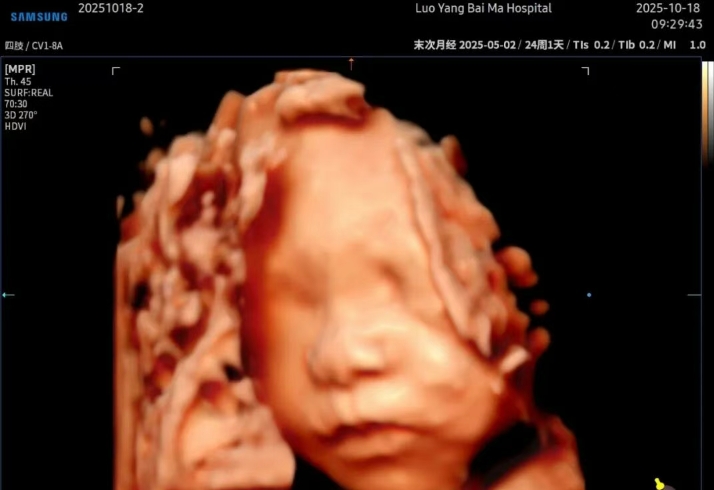

洛阳白马医院5D智能彩超,是目前先进的超声诊断技术,

广泛运用于对胎儿进行超声检查,具有智能化大数据分析诊断和人性化智能交互应用功能,

相比四维彩超,在排畸功能上更完善、观察范围更广、画面更清晰,能够多方位、

多角度观察宫内胎儿生长发育情况。

能栩栩如生的显示您未出生的宝宝在妈妈肚子里的实时动态。